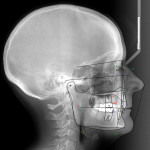

Cephalometric measurement of the interincisal angle provides valuable information in treatment planning and can help demonstrate the importance of orthodontically modifying the anterior tooth relationship prior to restorative treatment. An interincisal measurement of 125 to 135 degrees is considered to be an acceptable range of functional biocompatibility.2 This patient’s interincisal angle measured 165 degrees on the pre-treatment cephalometric analysis (Figure 5).